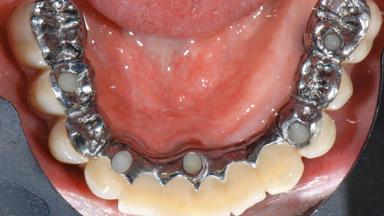

Repeated Acrylic Fractures on a Mandibular Fixed Full-arch Implant-supported Metal/Acrylic Prosthesis

A 77-year-old male patient was referred for the management of frequent and repeated acrylic fracture of his existing mandibular fixed full-arch implant-supported metal/acrylic prosthesis. He also complained about softtissue soreness and the lack of retention and stability of his maxillary removable partial metal/acrylic prosthesis. Both prostheses had been delivered two years previously as part of his full-mouth rehabilitation (caries, tooth wear, tooth fracture). His medical history revealed high blood pressure, controlled with the use of antihypertensive medication.